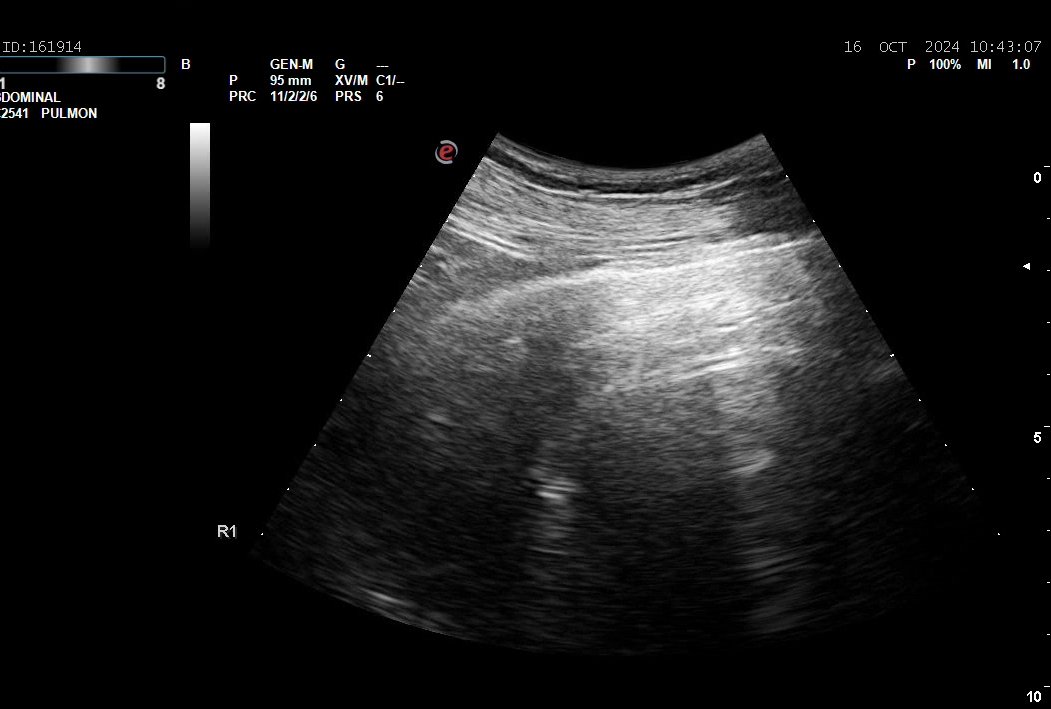

La eco a pié de cama muestra masa/atelectasia LID.